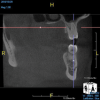

(4.) In a CBCT image axial view, the MB1 and MB2 canals are readily visible in tooth No. 14, and in the coronal view, these two separate canals can be seen to merge into a single apical opening.

Figure 4

(5.) In a CBCT image axial view, the MB1 and MB2 canals are readily visible in tooth No. 14, and in the coronal view, these two separate canals can be seen to merge into a single apical opening.

Figure 5